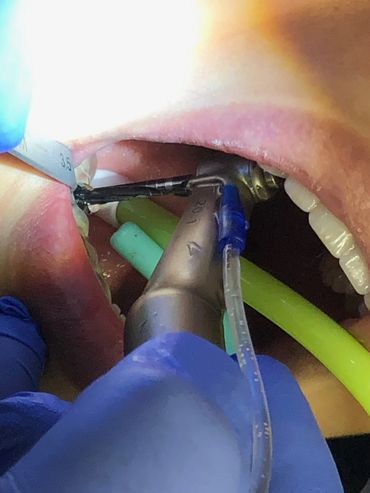

Keyless (one-handed) Guided Surgery

The Neodent GM Guided Surgery Kit is a compact, easy to use guided surgery system. Clinicians can provide CT scan, digital photos, and impressions to a laboratory for precise implant guide fabrication. Temporary teeth can be made and the lab will know the depth, angle, and timing of the connection of the implant. This allows you better esthetics and provides the patient teeth the same day with less chair time.